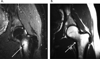

Methods: A total of 211 male and female collegiate track and field and cross-country athletes were followed prospectively through their competitive seasons. All athletes had preparticipation history, physical examination, and anthropometric measurements obtained annually. An additional questionnaire was completed regarding nutritional behaviors, menstrual patterns, and prior injuries, as well as a 3-day diet record. Dual-energy X-ray absorptiometry was performed at baseline and each year of participation in the study. Athletes with clinical evidence of bone stress injuries had plain radiographs. If radiograph findings were negative, MRI was performed. Bone stress injuries were evaluated by 2 independent radiologists utilizing an MRI grading system. The MRI grading and risk factors were evaluated to identify predictors of time to return to sport.

Results: Thirty-four of the athletes (12 men, 22 women) sustained 61 bone stress injuries during the 5-year study period. The mean prospective assessment for participants was 2.7 years. In the multiple regression model, MRI grade and total-body bone mineral density (BMD) emerged as significant and independent predictors of time to return to sport. Specifically, the higher the MRI grade (P = .004) and lower the BMD (P = .030), the longer the recovery time. Location of the bone injury at predominantly trabecular sites of the femoral neck, pubic bone, and sacrum was also associated with a prolonged time to return to sport. Female athletes with oligomenorrhea and amenorrhea had bone stress injuries of higher MRI grades compared with eumenorrheic athletes (P = .009).